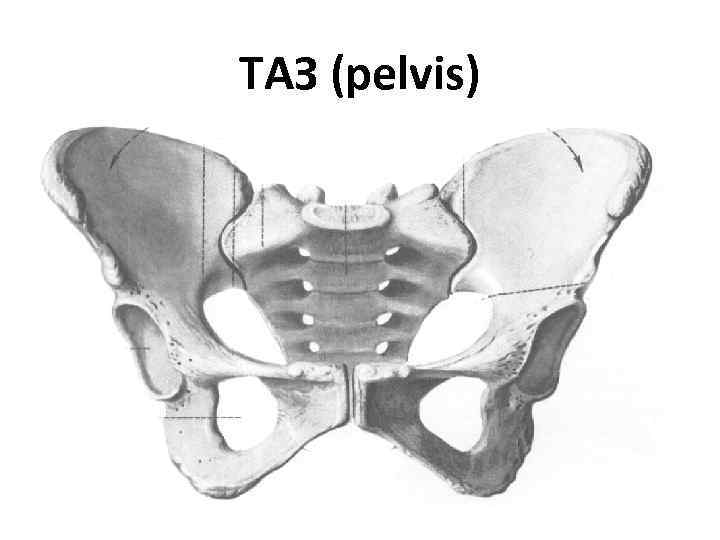

ТАЗ (pelvis)

Розміри таза Міжостьова відстань Міжгребенева відстань (23 -25 см) (25 -27 см) Міжвертлюгова відстань (31 -33 см) Крижовоклубовий суглоб (плоский) Лобковий симфіз

Розміри таза Анатомічна Зовнішня кон’югата (20 -21 см) (11, 5 см) Справжня кон’югата Тазова ось (10, 5 -11, 0 см) 60˚ Нахил таза (55˚-60˚) Пряма Діагональна кон’югата (9, 5 см) (12, 5 -13 см)